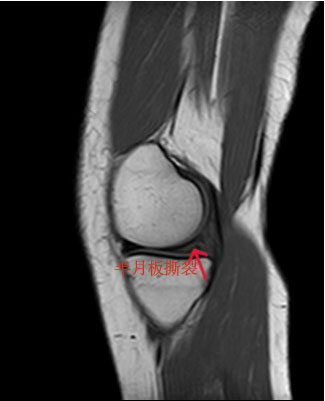

李女士,37岁,右膝关节疼痛伴活动受限3月,伴有跛行,上下楼梯疼痛,有蹲起困难,有卡感和交锁,门诊核磁检查提示:半月板撕裂。门诊以“右膝半月板撕裂”收入院。完善术前检查,明确无手术禁忌症后,应用缝合器技术将撕裂半月板缝回它原本的位置。

术前右膝关节冠状位核磁可见半月板在多个层面上出现高信号(红色箭头所指位置)